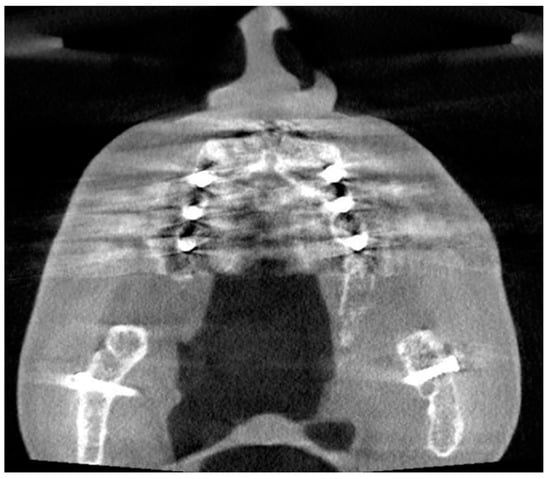

In total, 214 patients with CBCT images taken during 2017 were identified with a diagnosis of CRS. Of these patients, 139 were women (65%) and 75 were men (35%), with a median age of 62 years and with a range from 50 years to 89 years. Seven reports of the CBCT images were missing. Based on the reports, CRS of dental origin was suspected in 24/214 (11%) of the CBCT images due to AP diagnosed in the upper jaw (Figure 2). Artifacts were recorded in the reports in only four images, and an additional X-ray imaging examination was recommended twice due to the artifacts.

The origin of the artifacts in the CBCT images is given in Figure 5. The main origins of the artifacts were large dental fillings or crowns in the upper jaw, being present in 203/214 (95%) of the CBCT images (Figure 6). Endodontic fillings of the maxillary teeth were the reason for artifacts in 111/214 (52%) of the images (Figure 7), followed by fixed dental prostheses and dental implants (Figure 8) causing the artifacts in 28/214 (13%) and 5/214 (2.3%) of the CBCT images, respectively. Other implants in the maxillofacial area were found only in three CBCT images, resulting in artifacts in levels 2 and 3 (Figure 3).

Figure 2. The coronal (A) and sagittal (B) slices of the CBCT image present sinusitis and distinct apical periodontitis of the root-filled right maxillary molar D16 buccal roots (arrow).

AP is an inflammatory disorder of the tooth root caused by bacterial invasion of the pulp, such as in untreated dental caries. At first, AP appears as a widened periodontal ligament in the apex of the root, and possibly in only one of the roots of a molar. Therefore, evaluating AP in the CBCT image of paranasal sinuses requires a careful examination of each root considering the root anatomy. AP is the most common cause of CRS of dental origin due to the close relationship between the maxillary molar roots and the maxillary sinus floor (Figure 2). This study focused only on AP as a cause of CRS. However, other dental diseases can cause CRS, such as periodontitis, vertical bone loss, and endodontic-periodontic pathology, as well as iatrogenic causes, such as oroantral fistula, foreign bodies, misplaced roots, dental and root canal fillings, and sinus lift procedures [4]. These causes indicate that CRS of dental origin is not only a wide problem among those who cannot afford dental treatments, but also among those who can afford extensive treatments such as dental implants [20,30].